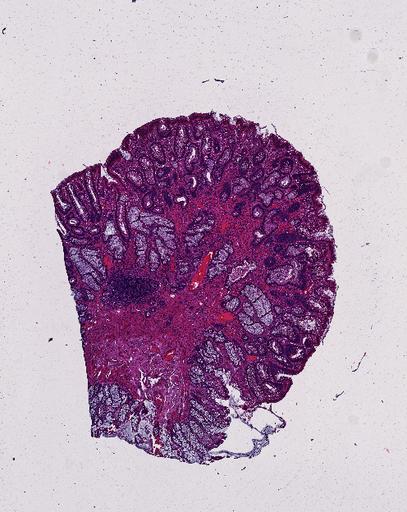

High‑resolution three‑dimensional (3D) tissue atlases promise to redefine how we study cellular architecture‑function relationships in human tissues. Large-scale consortia such as the Human Bimolecular Atlas Program (HuBMAP) systematically build detailed 3D organ maps by profiling serial tissue sections with single-cell spatial technologies. However, an accurate and efficient reconstruction method that can handle atlas-scale datasets remains elusive. We introduce Space-map, an open-source method that integrates single‑cell coordinates with optional histological image features to assemble serial sections into 3D models. Space‑map combines multi‑scale feature matching with large‑deformation diffeomorphic metric mapping, delivering global reconstructions while preserving local micro‑anatomy. To demonstrate the capability of Space-map, we generated a serially sectioned spatial transcriptomics (Xenium, ~2.9M cells) dataset and a spatial proteomics dataset (CODEX, ~2.4M cells). Applying Space-map to these single-cell spatial maps, we built three 3D models for both diseased (colon polyp) and reference colon tissues. These high-resolution 3D models showcase the intricate structure of the human colon across different states. Space-map is fast and highly efficient. We demonstrated its performance and accuracy using in‑house and public datasets. The result shows that Space‑map is 10 times faster and ~2‑fold more accurate than PASTE and STalign, making 3D atlas reconstruction more accessible. Our study provides a new robust and user-friendly software available at https://github.com/a12910/spacemap that can be easily applied for constructing molecular 3D tissue maps of human organs at single-cell resolution.